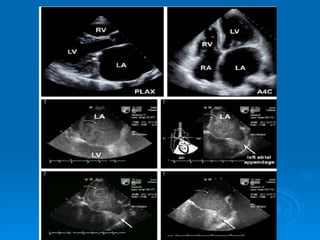

Echo-doppler Cardiaque Echographie bidimentionnelle: Épaississement de la valve Diminution d’ouverture valvulaire Aspect caractéristique en genou fléchi de la GVM Mesure de la surface mitrale Recherche de calcifications Recherche de thrombis intra auriculaire gauche Dilatation de OG Etude de l’appareil sous valvulaire

Echographie TM Diminution de l’onde E Diminution de la pente EF Mouvement paradoxal de la PVM DOPPLER Mesure du gradient diastolique OG-VG Mesure surface mitrale Mesure PAPS Critéres de sévérité: Gradient moyen supérieur a 10 mmhg Surface mitrale< 1 cm ² PHT sup 220 msec

Thrombus intra OG

Thrombus intra auricule gauche ETO

Echo-doppler Cardiaque Echographiebidimentionnelle: Épaississement de la valve Diminution d’ouverture valvulaire Aspect caractéristique en genou fléchi de la GVM Mesure de la surface mitrale Recherche de calcifications Recherche de thrombis intra auriculaire gauche Dilatation de OG Etude de l’appareil sous valvulaire

Echographie TM Diminutionde l’onde E Diminution de la pente EF Mouvement paradoxal de la PVM DOPPLER Mesure du gradient diastolique OG-VG Mesure surface mitrale Mesure PAPS Critéres de sévérité: Gradient moyen supérieur a 10 mmhg Surface mitrale< 1 cm ² PHT sup 220 msec